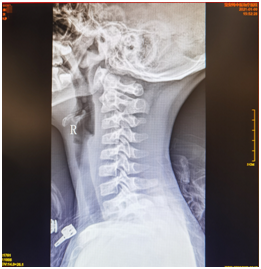

辅助检查:2021-01-09我院颈椎正侧位+开口位:颈椎轴线右侧旋转、侧弯,生理曲度轻度反弓。